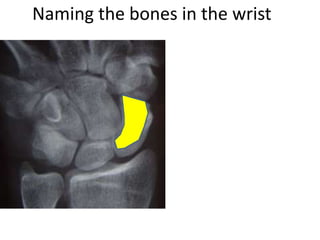

This document provides an overview of hand anatomy including:

- Naming the bones, joints, tendons, nerves and skin landmarks of the hand and wrist.